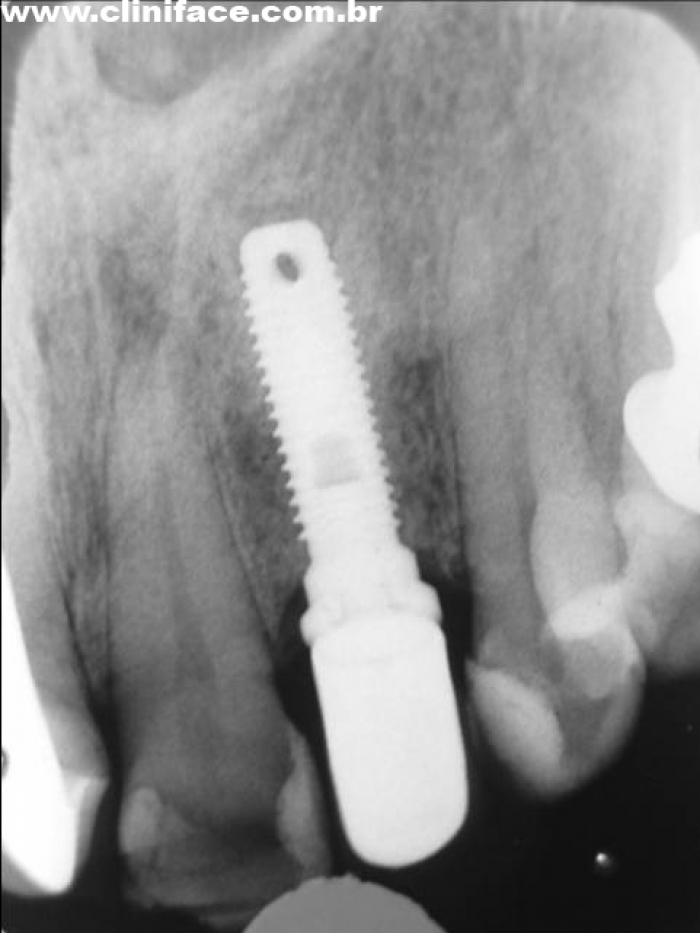

Rx atual (2009) de Implantes Nobel® e Próteses Instaladas nos elementos 12 e22, em 1998